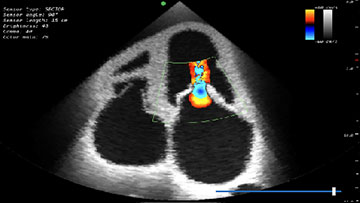

Модуль по трансторакальному УЗИ сердца

Модуль по трансторакальному УЗИ сердца на основе данных реальных пациентов

- Обучающий модуль по трансторакальному ультразвуковому исследованию сердца